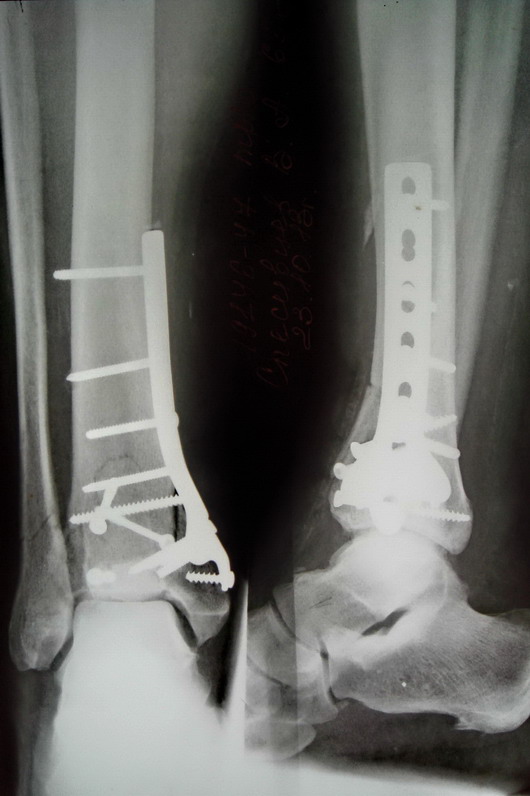

[Ortho] Перелом Пилона

Можно было бы вот такой пластиной попробовать